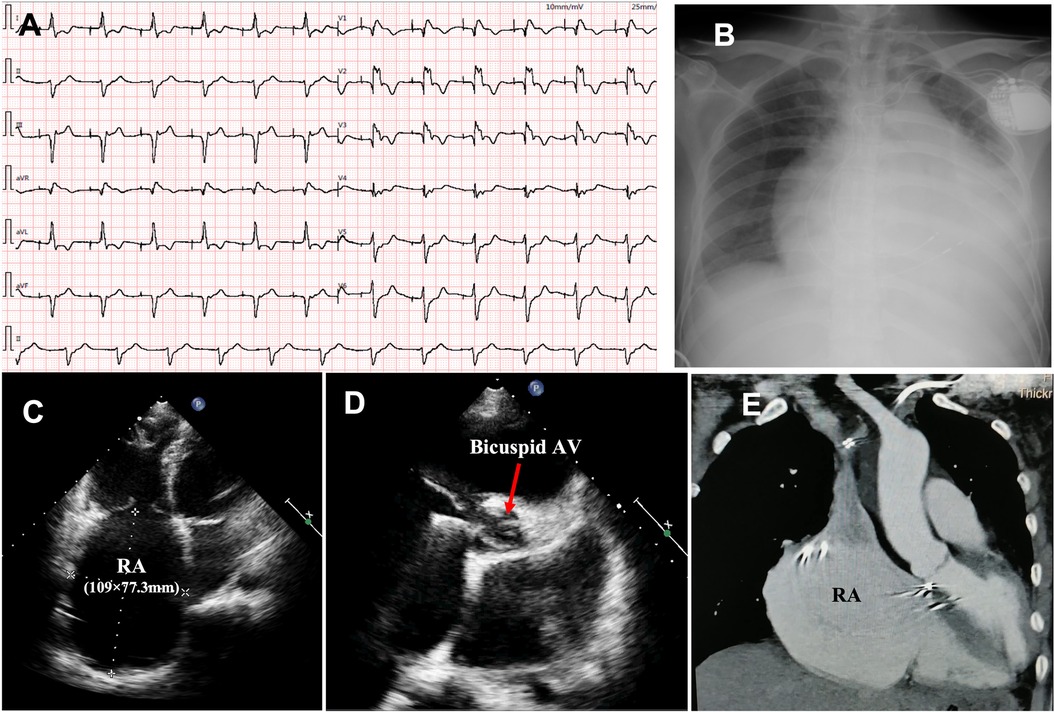

An Improved Genome-Wide Association Procedure Explores Gene–Allele Constitutions and Evolutionary Drives of Growth Period Traits in the Global Soybean Germplasm Population,Frontiers | Novel pathogenic variant in LMNA gene identified in a six-generation family causing atrial cardiomyopathy and associated right atrial conduction arrhythmias,SHOWROOM(ショールーム) | ライブ配信サービス,Frontiers | Unveiling the crucial roles of abscisic acid in plant physiology: implications for enhancing stress tolerance and productivity,小清水亜美 - Wikipedia